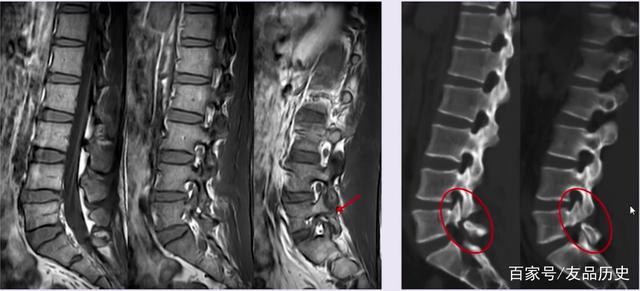

腰椎管狭窄症 微创通道下减压 经皮椎弓根螺钉内固定术

聊聊啥是腰椎间盘突出症?病因,分型,临床表现,诊断依据又是啥

x线可以检查腰椎外部结构是否正常,有无崩裂,滑脱,硬化等情况,如骨质

腰椎疼痛去拍片拍片时到底在干些什么呢